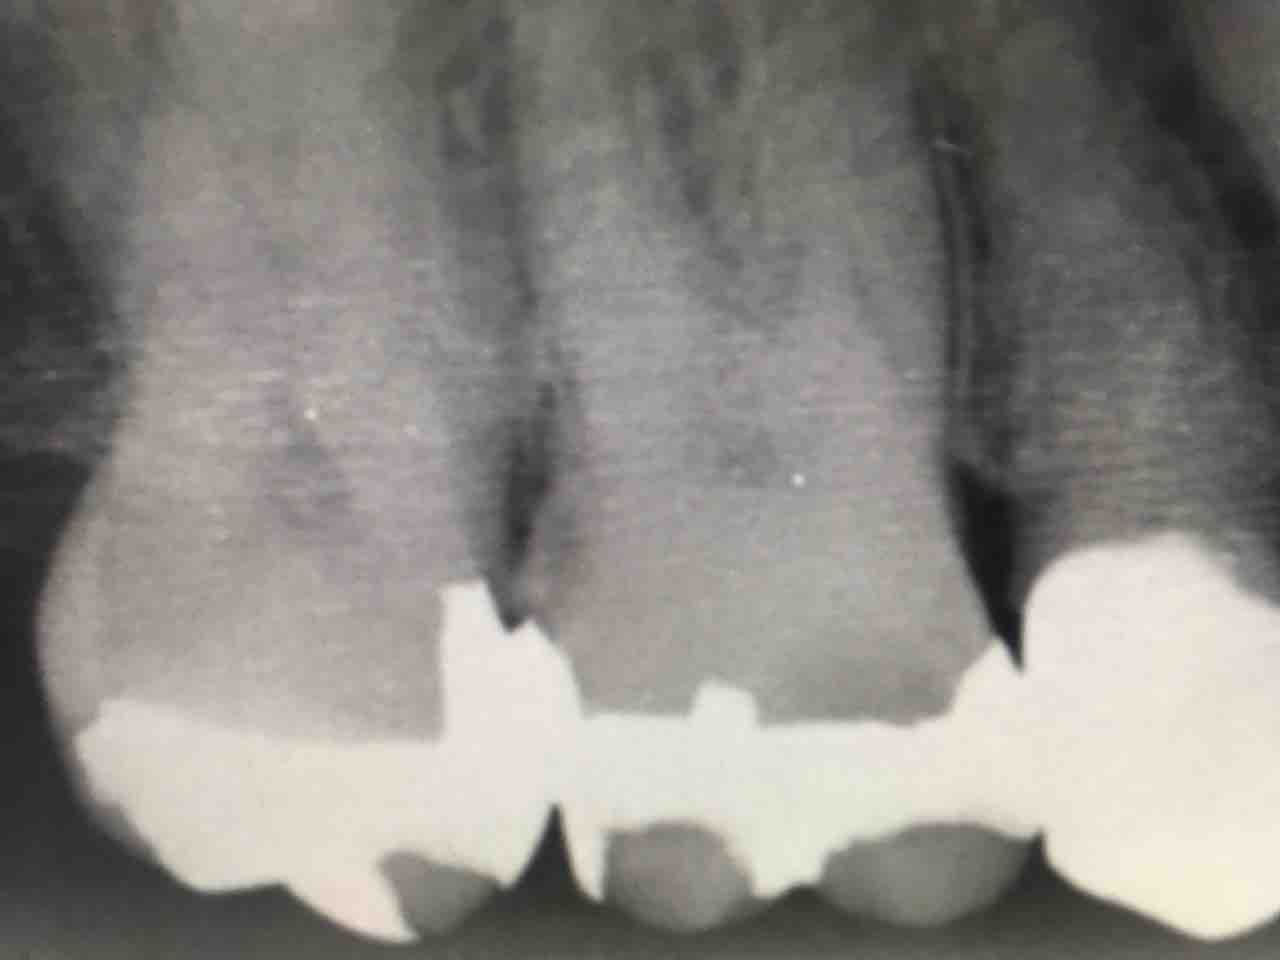

全て除去してこうなります↓

そして、皆さんは、こうやって写真を拡大すると歯科用顕微鏡があれば簡単に歯石が除去できると思われるかも知れません。

が、それは間違いです。

見えといっても、歯周ポケットの幅は健康で締まっていれば1mmあるかないかです。

今日のケースでも、0.8mm程度

1mm無い歯と歯肉の間。そして見える角度は限られて、更に器具の角度、挿入方向も限られる...

歯科用顕微鏡の処置は非常に制限される処置なのです